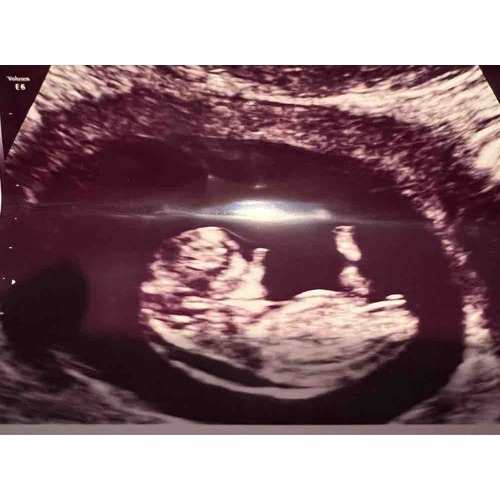

Bedankt voor jouw reactie! Mijn volgende afspraak is woensdag bij de vk. Wat de vk erbij zei was dat ze wachten tot de 13 weken echo te lang vond. Ze wilde er eerlijk over zijn en zei dat de nekplooi dikker dan gemiddeld is. Maar dit was wel zonder meeting, dus wat ze op het blote oog kon zien.

Ik vind je VK heel voorbarig. Je bent ten eerste nog geen 11 weken zwanger, pas vanaf 11 weken kan een nekplooi goed gemeten worden. Het vocht wat je nu ziet kan volgende week weg getrokken zijn.

Wij hebben dit ook gehad. Met 10+6 verdikte nekplooi te zien. Was op vrijdag. Op maandag voor een GUO toen was de nekplooi 7 mm en vocht rondom onze baby (hydrops) en hygroma colli.

Wij hebben exact hetzelfde meegemaakt. Termijn echo ook met 10+4 gehad en hier was vocht rondom de nek te zien maar ook bij het buikje. 2 weken in spanning gezeten tot de 13 weken echo. Uiteindelijk was er niks aan de hand... Ze hadden het niet mogen meten achteraf, echo was veelste vroeg. Hopelijk valt het bij jullie ook mee.